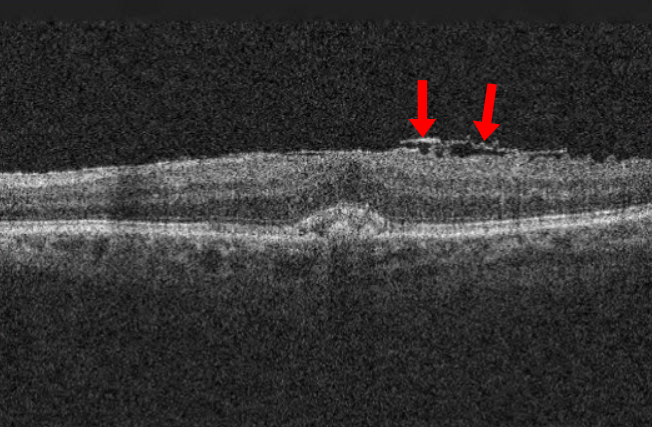

망막전막은 우리 눈에서 빛을 감지하고 뇌로 신호를 전달해 시력을 유지하는 핵심 부위인 망막의 앞 표면에 반투명한 막조직이 형성되면서 황반 기능에 이상을 일으키는 질환이다. 망막앞막, 황반주름 등으로도 불린다.

망막전막은 진행 속도가 비교적 느려 일상생활에 큰 불편이 없으면 경과 관찰을 하기도 한다. 보통은 충혈과 통증 없이 시력의 변화만 나타나기 때문에 눈을 한 쪽씩 가리며 스스로 '암슬러 격자' 검사를 해봐야 한다. 이때 선이 휘어지거나 끊어져 보이는 등 시력 저하가 뚜렷하다면 안과에서 망막 검사, 빛간섭단층촬영 등을 통해 질환 여부를 확인하는 게 바람직하다.